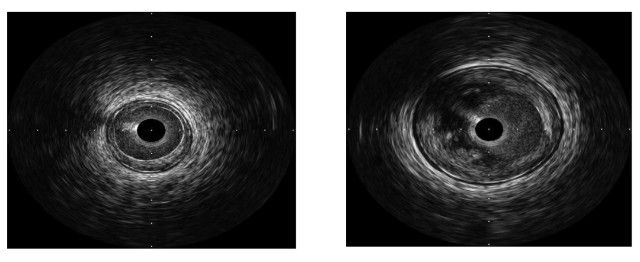

开立超声怎么导出图像步入冠脉精准化时代:开立高清IVUS获批上市_https://www.jmylbn.com_新闻资讯_第6张

左图为纤维性斑块,病变4点-7点部位为低回声区,回声密度和外膜及周围组织相似;右图6点-12点新月形脂质核、内可见不规则强回声,纤维帽菲薄。